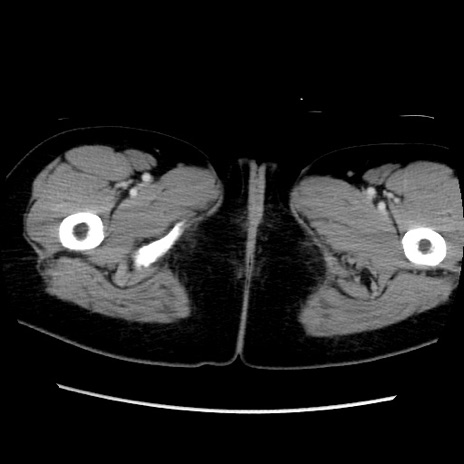

症例39(横断像)

【症例】40歳代女性

【主訴】上下腹部痛

【現病歴】2日目から下腹部痛あり。夜間は痛みで眠れなかった。昨日より上腹部痛と下痢が出現。臥位で痛みは軽快したため、休んでいた。本日になって臥位でも立位でも痛みが強くなってきたため救急要請。

【既往歴】子宮内膜症

【身体所見】部:平坦・軟、左上下腹部に圧痛あり、反跳痛あり。

【データ】WBC 21800、CRP 26.78